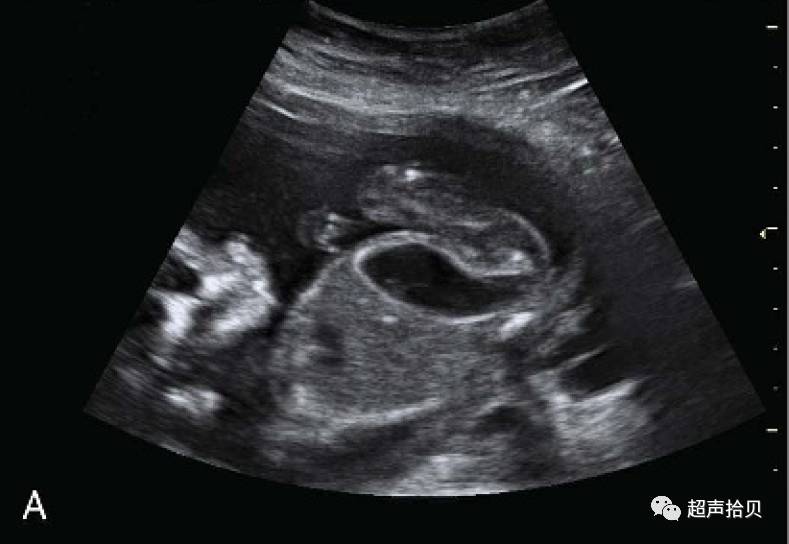

一位34岁的妇女,孕2,产1(健康3岁的女儿),没有相关的个人或家族史,妊娠12周孕早期超声检查,观察到胎儿,在左下腹靠后的位置低回声囊管状结构,并未发现其他异常:羊水正常,肾脏和膀胱正常;颈项透明层是在正常范围内,鼻骨是存在的,和静脉导管瓣评估显示没有改变。在早孕期筛查结果为三体13, 18也为阴性,。她在同一机构接受了16周的超声检查,也是同样的超声检查结果。在妊娠18周时进行排畸检查。我们验证了低回声图像出现如前所述:筒状囊肿(33毫米X10毫米X11毫米)位于左下腹部的膀胱后,与乙状结肠扩张(图1A)。

图1-A:在 18周扫描的扩张乙状结肠